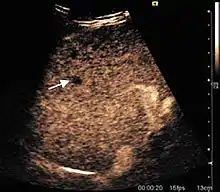

HCC appearance on 2D ultrasound is that of a solid tumor, with imprecise delineation, with heterogeneous structure, uni- or multilocular (encephaloid form). An "infiltrative" type is also described which is difficult to discriminate from liver nodular reconstruction in cirrhosis. Typically HCC invades liver vessels, primarily the portal veins but also the hepatic veins . Doppler examination detects a high speed arterial flow and low impedance index (correlated with described changes in tumor angiogenesis). The spatial distribution of the vessels is irregular, disordered. CEUS examination shows hyperenhancement of the lesion during the arterial phase. During the portal venous phase there is a specific "wash out" of ultrasound contrast agent (UCA) and the tumor appears hypoechoic during the late phase. Poorly differentiated tumors may have a stronger wash out leading to an isoechoic appearance to the liver parenchyma during portal venous phase. This appearance was found in approx. 30% of cases. The described changes have diagnostic value in liver nodules larger than 2 cm.

The suggestive appearance of early HCC on 2D ultrasound examination is that of hypoechoic nodule, with distinct pattern, developed on cirrhotic liver. Hypoechoic appearance is characteristic of moderate/poorly differentiated HCC, with low or absent fatty changes. Rarely, HCC may appear isoechoic, consist of a tumor type with a higher degree of differentiation and therefore with slower development. Another common aspect is "bright loop" or "nodule-in-nodule" appearance, hypoechoic nodules in a hyperechoic tumor.